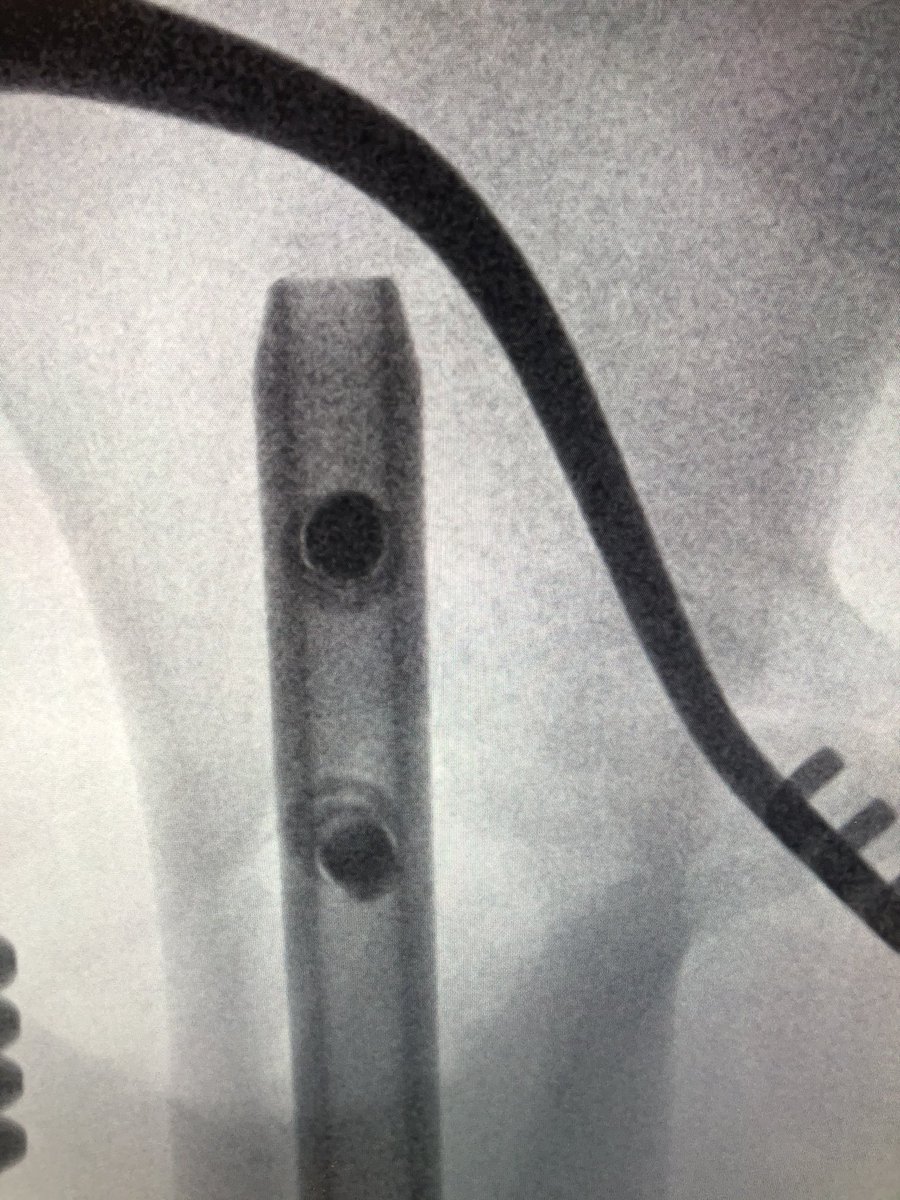

[2/5] From my prior years of being “alone” (no residents) I like to make life easier for myself so this was automatic small incision & clamp. I use fluoro heavily to help me with incision planning, so here I am drawing lines along freer to place my incision in the best position.